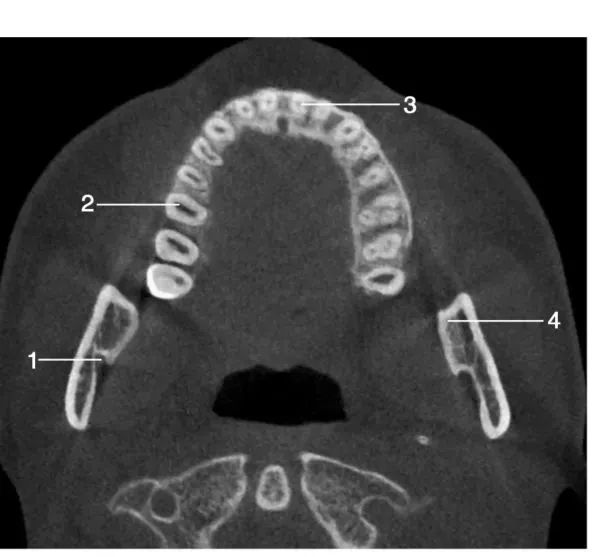

1、水平位影像经下颌体颏孔区层面水平位图像1.颏孔 ; 2.右下尖牙牙根; 3.左下第一前磨牙牙根; 4.下颌体

经下颌后牙牙冠处层面水平位图像